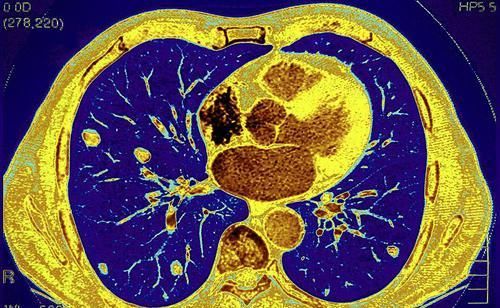

【肺癌会引起咳嗽?主要有这4个特征,早期发现或能保命】1、出现血痰

肺癌引发的咳嗽是有特点的,很多人在咳嗽的过程中,会发现痰液分泌量也多,痰液中甚至会有血丝、血块出现。一旦存在这种情况,说明肺癌可能正处于发展过程中,因为在肺癌发病时,会有刺激性的干咳、咳嗽,较为剧烈时肿瘤破裂出血。

本身肺部的肿瘤血液供应丰富,质地脆弱,剧烈咳嗽受到刺激,肿瘤破裂出血后血液会跟痰液混合,容易出现痰液中有血液的情况。因此,经常在咳嗽的时候咳痰,有带血丝,血块的痰液分泌出来,都说明肺癌可能形成。